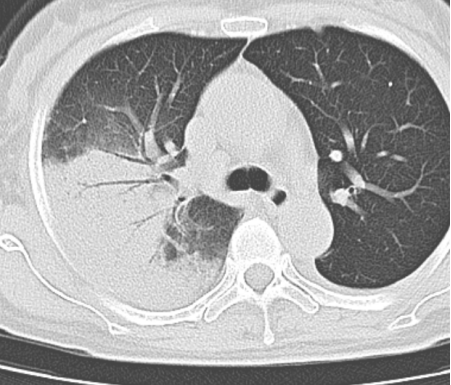

遂至我院感染科门诊就诊,完善肺部CT提示右上肺大叶性肺炎、双侧胸腔积液。入院后,主任查阅了患者的检查、检验报告单,并了解到其家中饲养几十只鸽子后,找出了她反复高热的元凶——鹦鹉热衣原体。

经积极治疗,李女士症状逐渐好转,出院前复查肺部CT,肺部病灶明显吸收。